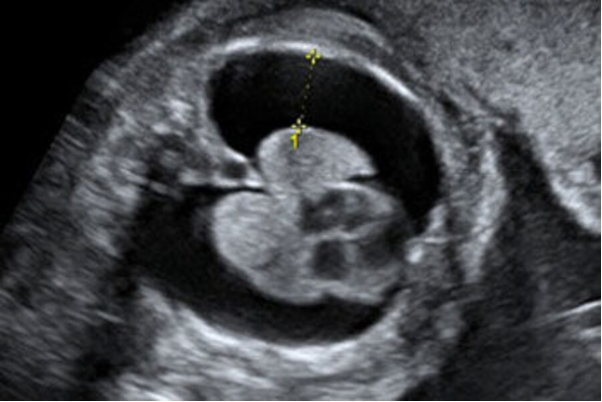

Theo BSCKI. Vương Thị Bích Thủy - Bác sĩ Trung tâm Y học Bào thai, Bệnh viện Đại học Phenikaa (PhenikaaMec), chọc hút dịch màng phổi thai nhi dưới siêu âm là thủ thuật can thiệp bào thai nhằm dẫn lưu lượng dịch bất thường tích tụ trong khoang màng phổi. Thủ thuật được thực hiện bằng kim chuyên dụng, đi qua thành bụng mẹ, tử cung và tiếp cận khoang màng phổi thai nhi dưới sự hướng dẫn trực tiếp của siêu âm.

Việc theo dõi hình ảnh thời gian thực giúp bác sĩ kiểm soát chính xác vị trí kim, lượng dịch được hút ra và kịp thời điều chỉnh thao tác nếu phát hiện bất thường, từ đó hạn chế tối đa nguy cơ biến chứng cho cả mẹ và thai nhi. Can thiệp sớm trong tử cung giúp cải thiện chức năng phổi và tuần hoàn của thai.

BSCKI. Vương Thị Bích Thủy cho biết: "Dưới hướng dẫn của siêu âm, bác sĩ đưa kim nhỏ vào khoang màng phổi thai nhi để hút dịch. Sau can thiệp, thai phụ được theo dõi sát tại bệnh viện từ 24–48 giờ nhằm phát hiện sớm các biến chứng như rỉ ối, co tử cung hay tái tích tụ dịch. Thai phụ cần theo dõi sát theo hướng dẫn của bác sĩ, tái khám đúng hẹn nhằm phát hiện sớm nguy cơ tái tích tụ dịch và đảm bảo an toàn cho thai nhi đến khi sinh."